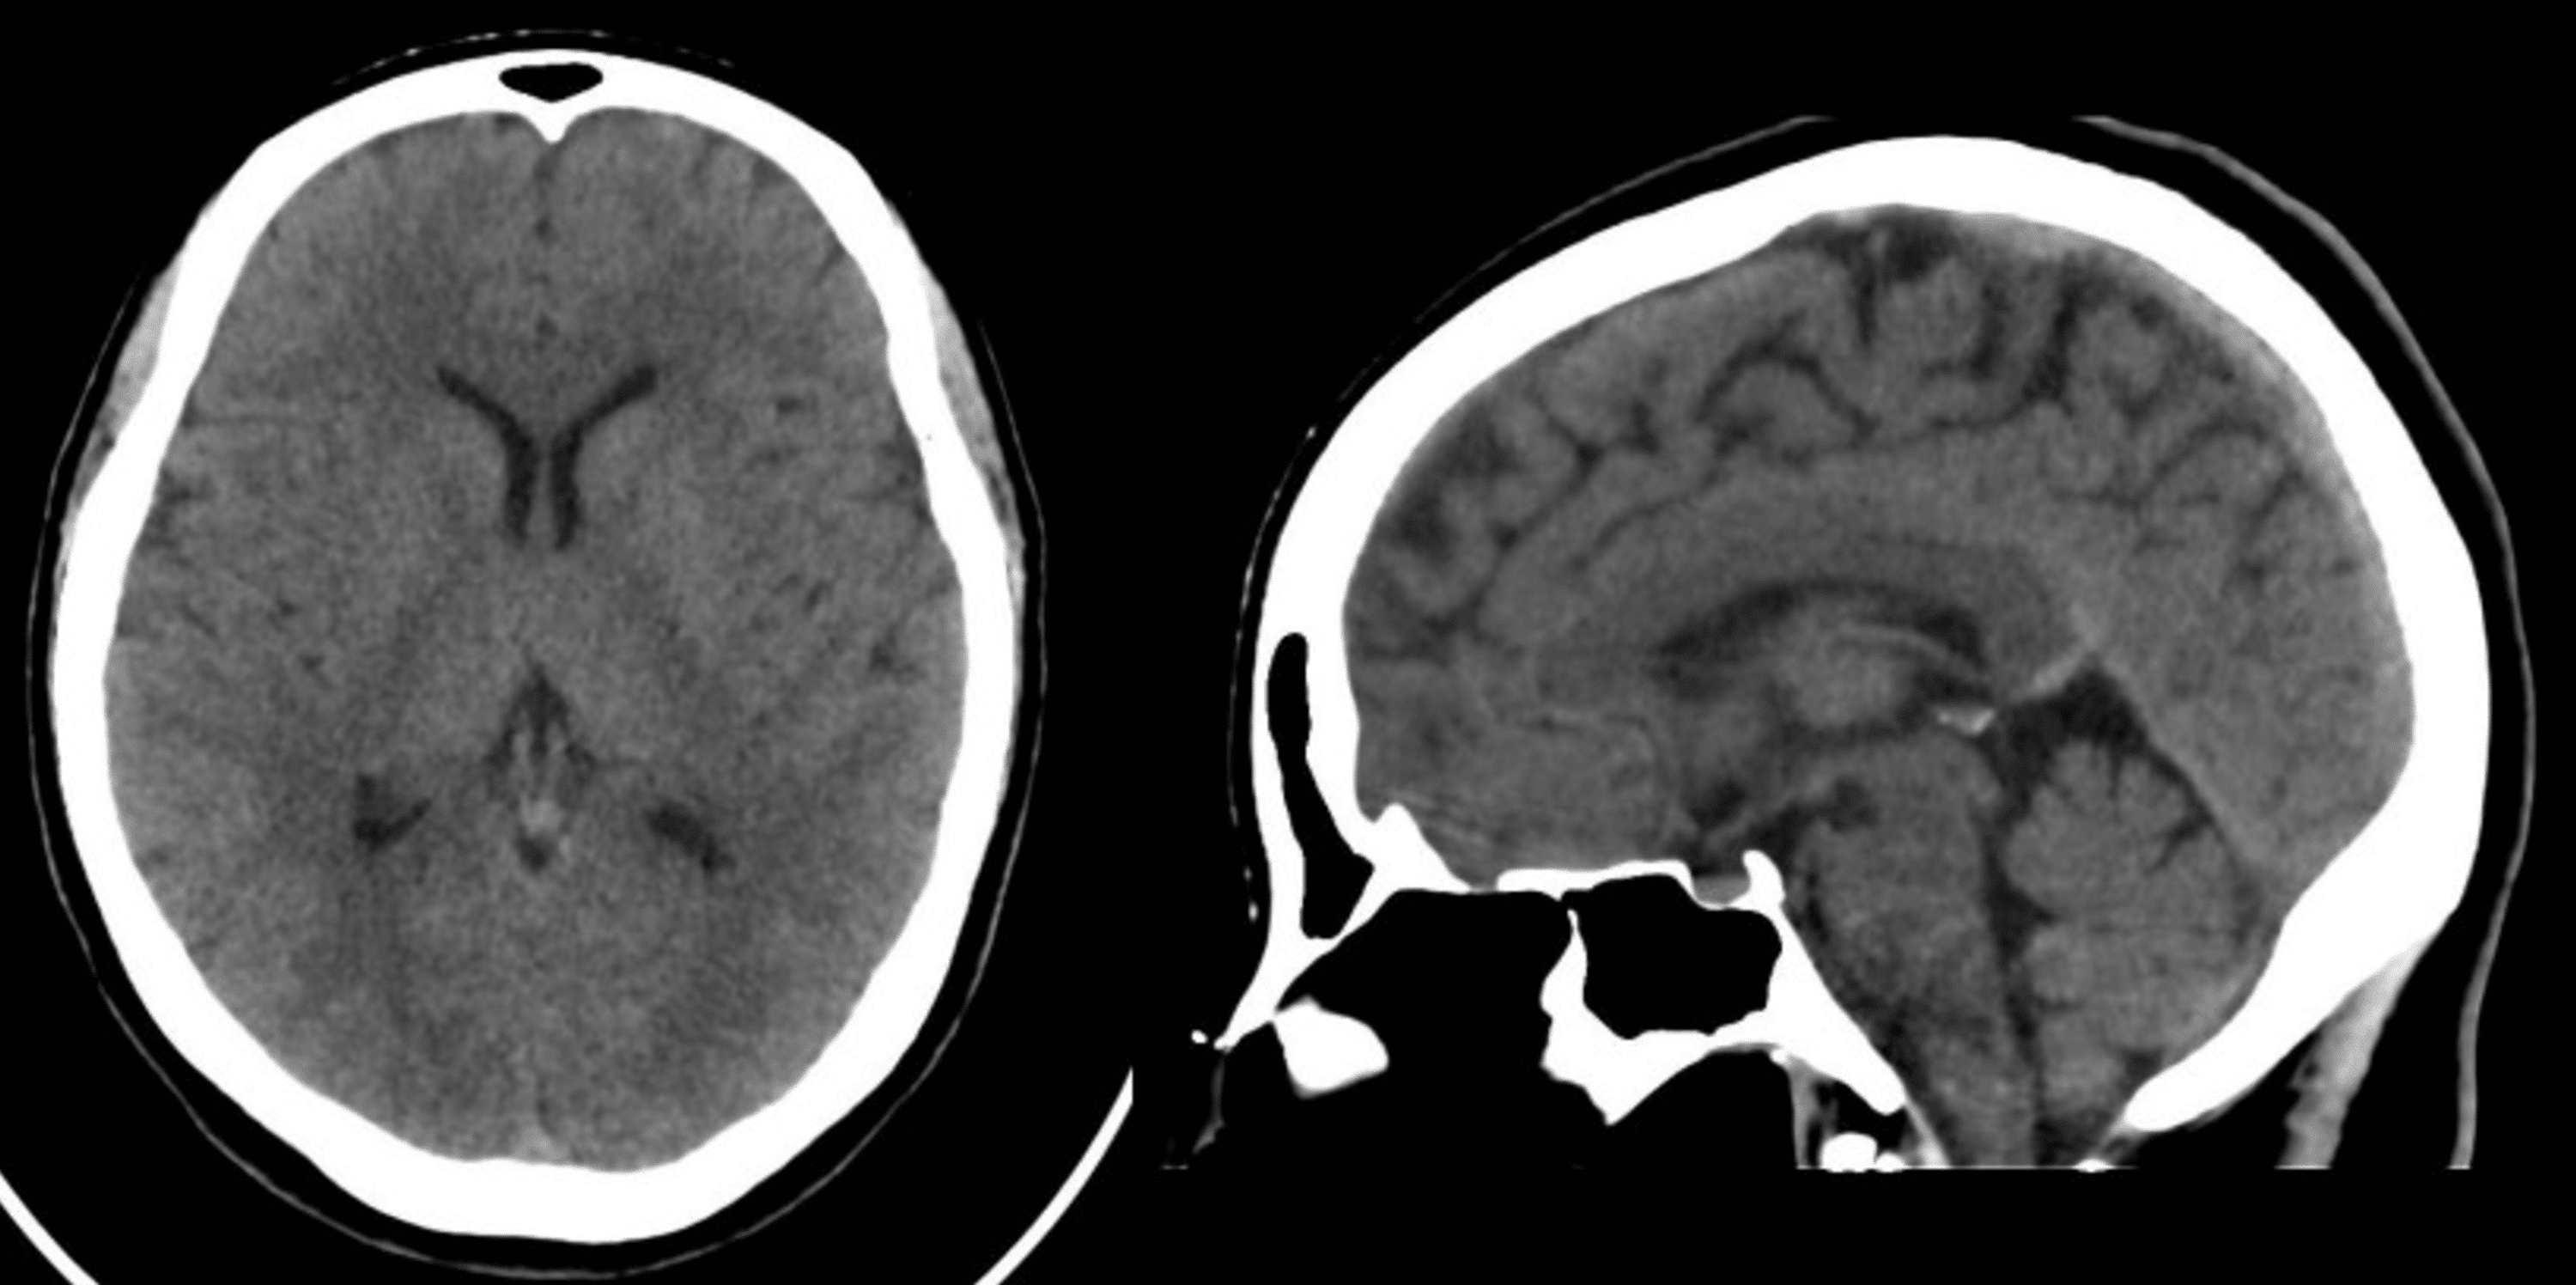

71yearold man with sudden headache and hemianopsia. A , CT scan shows... Download Scientific

From www.researchgate.net

71yearold man with sudden headache and hemianopsia. A , CT scan shows... Download Scientific Ct Scan For Headaches ahs consensus clarifies when clinicians should consider ct and mri scans for patients being assessed for migraine. Learn when and why you may need a ct. ct scans cannot diagnose migraine, but they can help rule out other conditions that may cause headaches. many headaches can be clinically diagnosed through imaging. Your doctor will likely examine you. Ct Scan For Headaches.